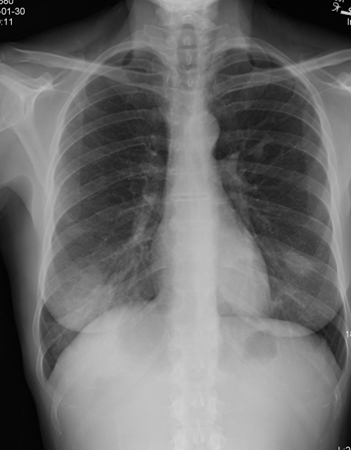

Organising pneumonia

Chest x-ray showing bilateral patchy infiltrates

From the collection of Gary R. Epler, MD